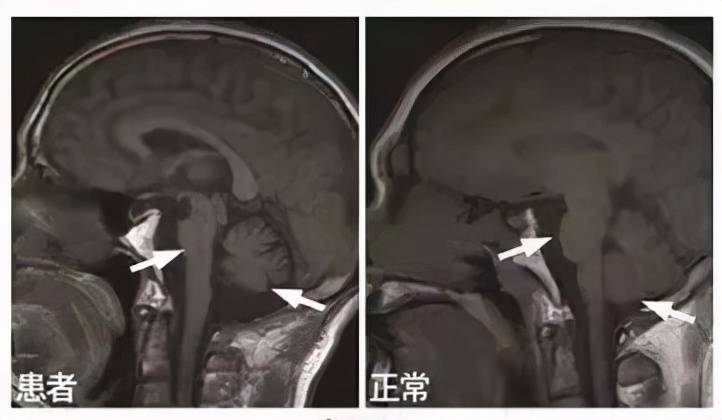

图 |核磁提示脑桥十字征

⑥MRI核磁表现壳核、小脑中脚、脑桥或小脑萎缩;

【诊断|【小帕讲故事】诊断多系统萎缩1、2、3】②MRI核磁表现壳核、小脑中脚或脑桥萎缩;